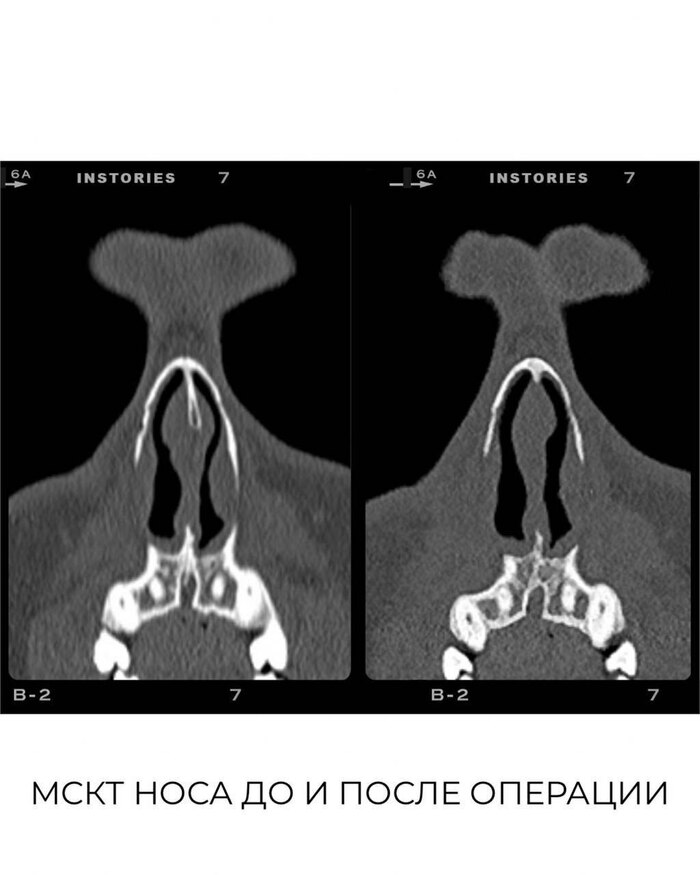

Уважаемые пациенты, обращаем ваше внимание на отзыв на сайте pikabu от нашего пациента. Пациент в своём обращении выражает недовольство проведенной операции, опираясь на суждение, что нос после операции стал намного хуже, что в носу появились чужеродные импланты.⁣⁣

Во время операции, у пациента оставившего отзыв, мы обнаружили следы предыдущей операции в виде резекции переднего отдела хрящевой части перегородки носа. Ранее пациенту уже выполняли септопластику в другом медицинском учреждении, но он это скрыл!⁣⁣ И естественно исправление чужого вмешательства, это уже совсем другая операция, нежели первичная ринопластика. Если бы нам было известно о ранее проведенной операции, то план лечения и оперативного вмешательства был бы другой. Но пациент предпочел скрыть от нас эту информацию, что не допустимо со стороны пациента, т.к. сокрытие от врача информации о своем здоровье может приводить к негативным последствиям.

Во время нашего вмешательства была выполнена вторичная ринопластика, это усложнило и удлинило саму операцию. Стоимость данной операции по факту должна быть больше.⁣⁣

Естественно, никаких чужеродных имплантов и подобного установлено не было. ⁣⁣

Хотелось бы еще уточнить, что данным пациентом была проведена медицинская экспертиза, спустя 3 месяца после операции, хотя это грубые нарушения,т к подобного рода экспертизы нельзя проводить раньше года после окончания операции. Потому что финальный результат можно оценивать только спустя год, никак не раньше. А так же пациент подал в суд на врача, но дважды не явился на заседания, а после и вовсе отозвал свой иск, что еще раз доказывает, что пациент не уверен в своей правоте и не готов был ее отстаивать. Мы же напротив готовы были доказывать нашу правоту и идти на диалог.

Прикрепляем отзыв пациента, опубликованный на сайте (1,2,3 фото в каруселе) а также КТ до операции, снимки с операционного стола и фото до/после спустя 3 месяца после операции.⁣⁣